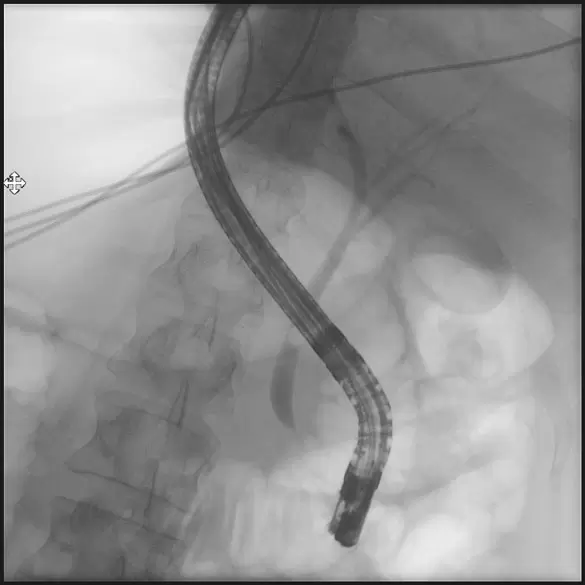

Gallengangsdarstellung (ERCP)

Mit Hilfe eines Spezialendoskops wird über einen dünnen Schlauch (Katheter) Kontrastmittel in den Gallengang und/oder den Bauchspeicheldrüsengang eingebracht und mittels Röntgenaufnahmen dokumentiert. Wenn Gallengangssteine vorliegen, können diese mit Hilfe eines kleinen Ballons oder Körbchens aus dem Gang entfernt werden. Bei einer Gallengangsengstelle (Stenose) oder Engstelle im Bauchspeicheldrüsengang können diese durch Einbringen eines Kunststoffröhrchens (Stent) überbrückt werden. Diese Untersuchung erfolgt immer mit einer Sedierung (Schlafspritze) und erfordert einen kurzen stationären Aufenthalt.